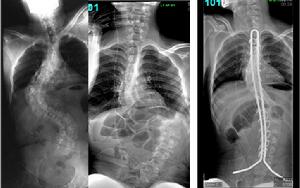

圖2-2:特發性脊柱側凸手術前後對比:男,22歲,術前主胸彎62°,術後矯正為23°